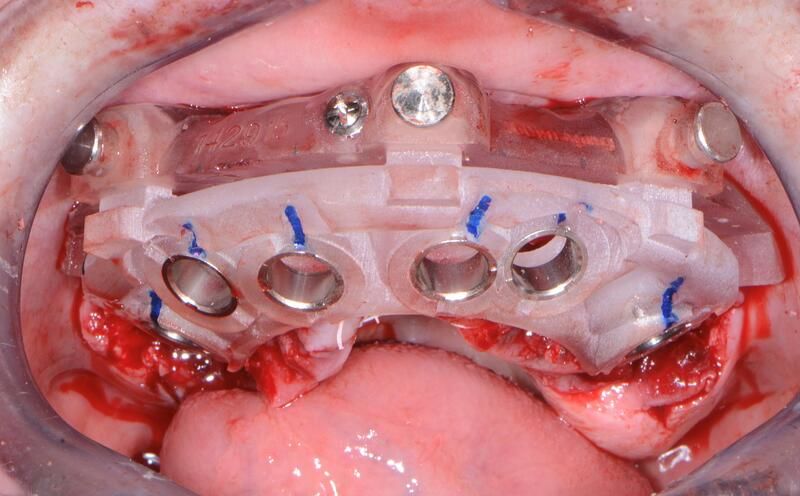

術(shù)中過(guò)程